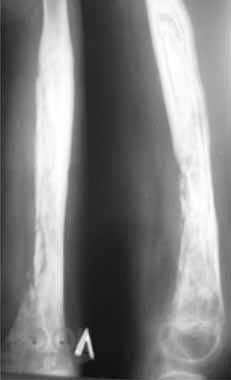

В пособии освещены современные концепции этиопатогенеза наиболее распространенных хирургических заболеваний детского возраста – гнойно-воспалительных заболеваний мягких тканей; различных форм гематогенного остеомиелита; деструктивных пневмоний; бронхоэктатической болезни; гнойно-воспалительных заболеваний мочевыделительной системы и органов брюшной полости – их диагностика и дифференциальная диагностика, современные методы консервативной терапии и оперативного лечения; критерии диагностики сепсиса и принципы рациональной антибиотикотерапии у детей. Пособие предназначено для студентов, обучающихся по специальности «Педиатрия», «Лечебное дело», «Медико-профилактическое дело».